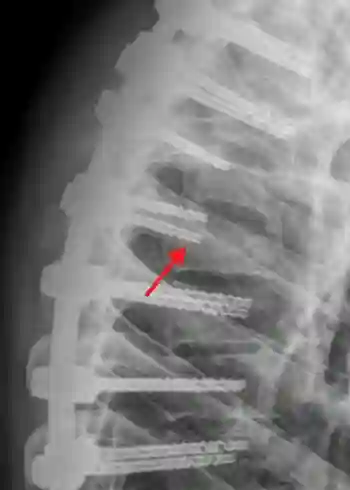

Als Indexschrauben bezeichnet man Pedikelschrauben, die bei Wirbelkörperfrakturen direkt im gebrochenen Wirbelkörper platziert werden. Die Indexschraube wird zusätzlich im gebrochenen Wirbel selbst verankert, sodass damit sich die Stabilität der Konstruktion erheblich erhöht.

Darstellung einer Indexschraube in einem sagittalen Röntgenbild (roter Pfeil) bei einem Patient mit einer langstreckiger dorsalen Spondylodese.